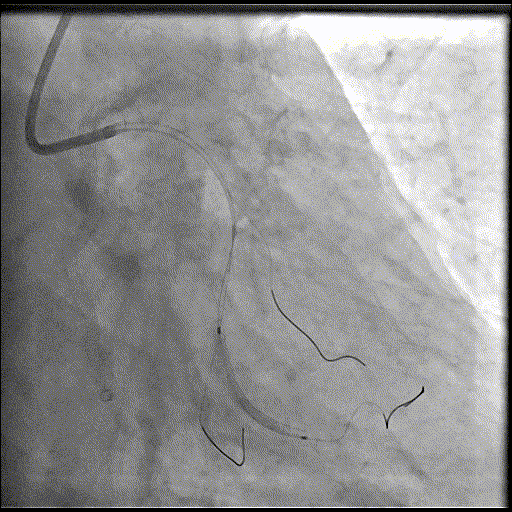

手术经过

导丝到位

当指引导管冠脉开口到位后,选择三根对应导丝分别送入LAD、D1、D2远端。

球囊预扩

选择不同尺寸的预扩球囊逐级预扩张病变,复查造影狭窄减轻不明显。为了解血管真实情况,遂启用IVUS检查。

术前腔内影像学IVUS指导

IVUS提示血管内钙化严重,最小管腔面积不足 4mm²;遂考虑启动IVL治疗。

冲击波球囊治疗

2.5*12mm@4atm 冠脉血管内冲击波导管反复进行8个周期治疗,经IVUS检查提示最小管腔面积增加至4.88mm²;随后选取后扩张球囊对病变行扩张治疗。

支架植入并后扩

于LM-LAD依次植入两枚药物洗脱支架,经非顺应性球囊后扩张支架,复查造影&IVUS提示血管内钙化仍较重,支架贴壁不良,遂再次启动IVL治疗。

再次冲击波球囊治疗

3.0*12mm@4atm 冠脉血管内冲击波导管反复进行5个周期治疗,并选取后扩张球囊对病变行扩张治疗。最终复查造影提示残余狭窄小于10%,未见夹层及血肿,TIMI血流3级。